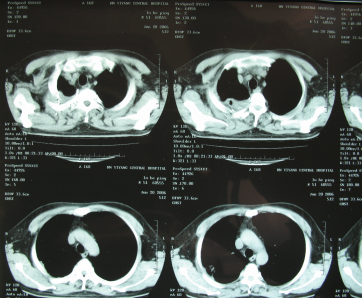

手术后CT显示

回家之后,鲁叔遵从医嘱,1月21日便去当地医院复查,CT显示肿瘤从原来的10×10cm缩小到2.6×1.3cm。“那个医生很吃惊,以为机器故障,又为我免费做了一次检查。”更让人感到吃惊的是,术后三个月他的肿瘤完全消失。事实上,肿瘤的完全消失不仅仅是治疗起作用,术后的康复也很关键。鲁叔从熬夜抽烟喝酒到后来戒烟戒酒生活作息规律,心态保持着乐观,并坚持上班不断充实自己,以最好的状态面对每一次复查,直到2020年7月,他的身上依旧无任何肿瘤复发迹象。“从04年的时候我每天都在计算,算着自己还有多少天,但是我现在已经从100天活到了第60个100天。”